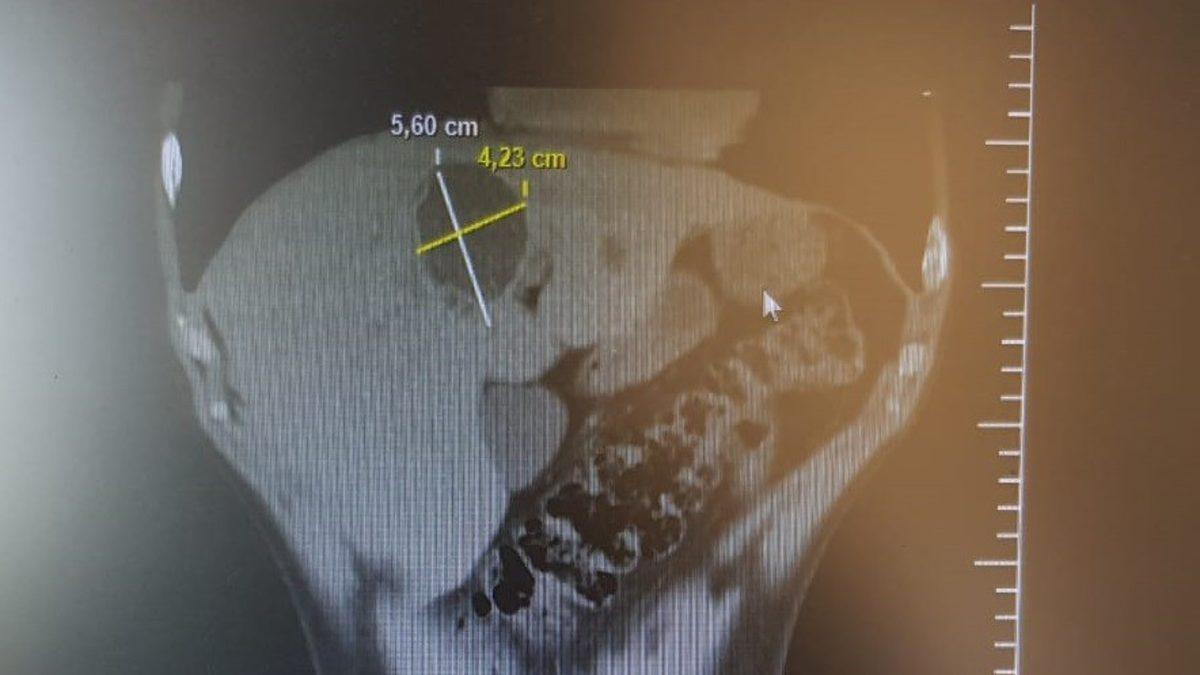

Bilecik Devlet Hastanesinde tedavi altında bulunan Sadık Akşehir (40) hasta karaciğer kist hidatik (hayvan kisti) kapalı kist ameliyatı (laparoskopik kistektomi) oldu. 5,60 ile 4,23 santimetre çapındaki kist 3 saatlik bir ameliyatın ardından alınarak, hasta 3 gün taburcu edildi. Hasta eski sağlığına kavuşurken, ameliyatı yapan Genel Cerrah Uzmanı Op. Dr. Süleyman Deniz Kahraman’a teşekkür etti.